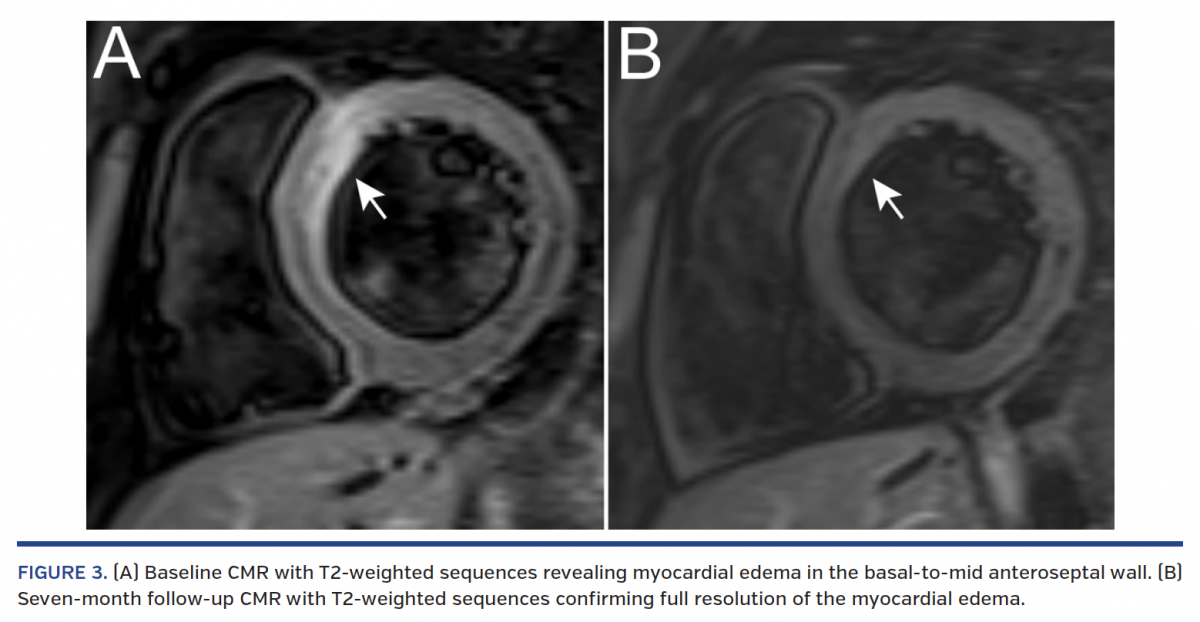

A 22-year-old, obese male smoker with untreated hyperlipidemia and family history of coronary artery disease presented with chest pain and ST-segment elevation in anterolateral leads at ECG following heavy marijuana and alcohol abuse. Coronary angiography showed a moderate stenosis in the proximal left anterior descending (LAD) coronary artery along with distal embolization (Figure 1A; Video 1). No concomitant coronary stenoses were noted, and TIMI 3 flow was present in the LAD. Optical coherence tomography (OCT) revealed plaque erosion with massive thrombi involving the distal left main coronary artery (LMCA) and ostial to mid LAD (Figure 1A; Video 2), along with preserved lumen area of the LAD. Given the diffuse extent of non-obstructive CAD involving the LMCA on OCT, aggressive medical thera-py with glycoprotein IIb/IIIa blocker, aspirin, ticagrelor, and high-dose statin was initiated. At discharge, cardiac magnetic resonance (CMR) imaging showed subendocardial infarction in the basal anteroseptal and lateral walls, and transmural infarction in the apex (Figure 2). After 3 months, repeat angiography with OCT demonstrated a non-obstructive lesion with fully healed fibroatheroma (Figure 1B; Videos 3 and 4). At 7 months, the patient was asymptomatic and control CMR showed preserved left ventricular function with resolution of myocardial edema (Figure 3; Video 5).